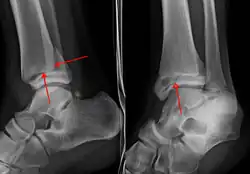

On X-rays, there can be a fracture of the medial malleolus, the lateral malleolus, or of the anterior/posterior margin of the distal tibia. [17] If both the lateral and medial malleoli are broken, this is called a bimalleolar fracture[18]. If the posterior malleolus is also fractured, this is called a trimalleolar fracture. [19]

A triplane fracture of the ankle as seen on plain X-ray

A triplane fracture of the ankle as seen on CT